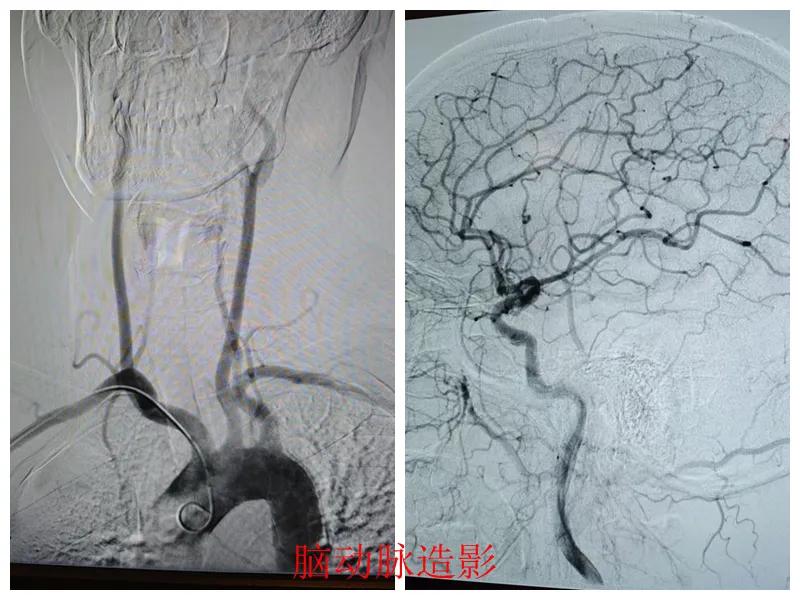

心腦聯(lián)防 腦心同治——市二院開展常態(tài)化心腦聯(lián)合造影

近日,市二院心血管內科聯(lián)合介入科為患者成功實施了“心腦同治”聯(lián)合造影手術,標志著醫(yī)院在“心腦同治”介入治療方面取得了顯著進展,為同時合并心腦血管疾病的患者查清了病癥,取得了良好的診療效果。

患者張某,47歲,因胸悶、左上肢麻木20天到市二院心血管內科就診,結合既往冠脈CTA、頭頸聯(lián)合CTA結果、高血壓病史以及入院后的輔助檢查結果,診斷為冠狀動脈重度狹窄、頸動脈狹窄。

經(jīng)王瑾院長和心血管內科、介入科多學科專家會診后,決定為患者進行冠狀動脈和腦血管聯(lián)合造影檢查,一次性完成心腦血管評估,并同步開展腦血管及冠心病介入治療。

術前準備完善后,在王瑾院長帶領下,心血管內科主任李慧新、影像科主任宋貴良、副主任醫(yī)師趙進科等緊密協(xié)作,成功為患者實施了冠狀動脈造影及腦動脈造影兩項檢查。冠狀動脈造影結果提示:患者右冠狀動脈慢性閉塞,腦動脈造影提示腦血管多支狹窄病變。

術后,根據(jù)造影檢查結果,科室團隊為患者制定了個體化的治療方案,經(jīng)過一段時間的規(guī)范化治療,患者很快便康復出院。